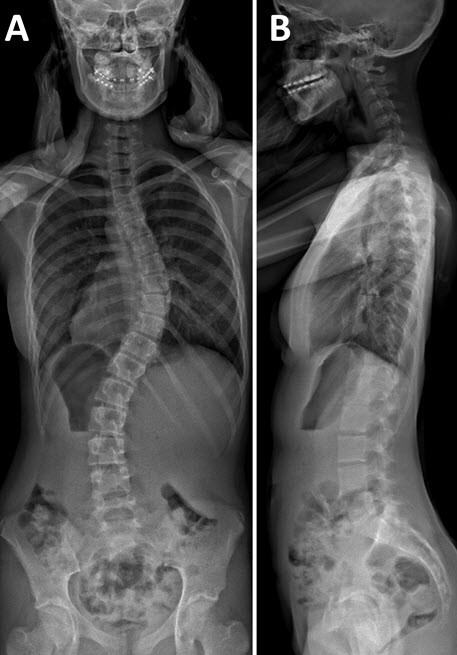

«Skolios» bedeutet «krumm» in Altgriechisch. Der Begriff umschreibt treffend das vorliegende Krankheitsbild: Bei einer Skoliose liegt eine seitlich verkrümmte Wirbelsäule vor, die mit einer Verdrehung der Rückenwirbel einhergeht. Die Skoliose zeichnet sich zudem dadurch aus, dass die Muskulatur nicht in der Lage ist, die Wirbelsäule wieder aufzurichten. Symptome entstehen meist erst bei einer starken Ausprägung und äussern sich je nach Ausmass unterschiedlich: in Form von Verspannungen, Rückenschmerzen, Rippenbuckel, Lendenwulst, Taillendreieck-Asymmetrie, einem schiefen Becken oder unterschiedlich hoch stehenden Schultern.

Bei Kindern und Jugendlichen lenkt die Wirbelsäule das Wachstum und sorgt für eine gesunde Entwicklung des Brustkorbs und der Lunge. Eine Skoliose im Kindes- oder Jugendalter kann vielfältige Folgen haben – von einer Fehlfunktion der Wirbelsäule bis hin zu einer abnormalen Entwicklung des Körpers mit Deformität des Torsos. Nebst kosmetischen Problemen können Gefühlsstörungen, Schmerzen oder sogar Lähmungen und Atembeschwerden auftreten.